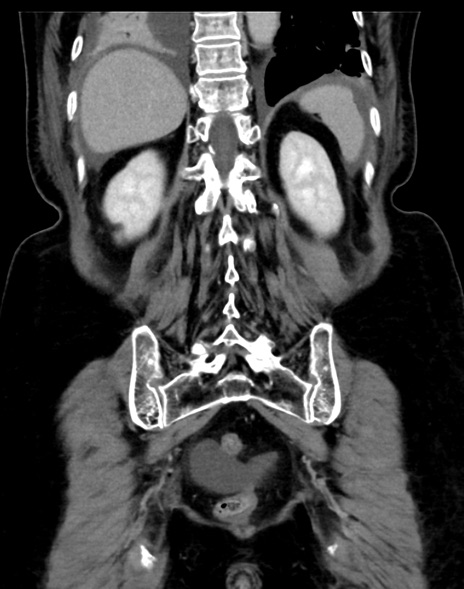

症例13 CT(冠状断像)1日半後